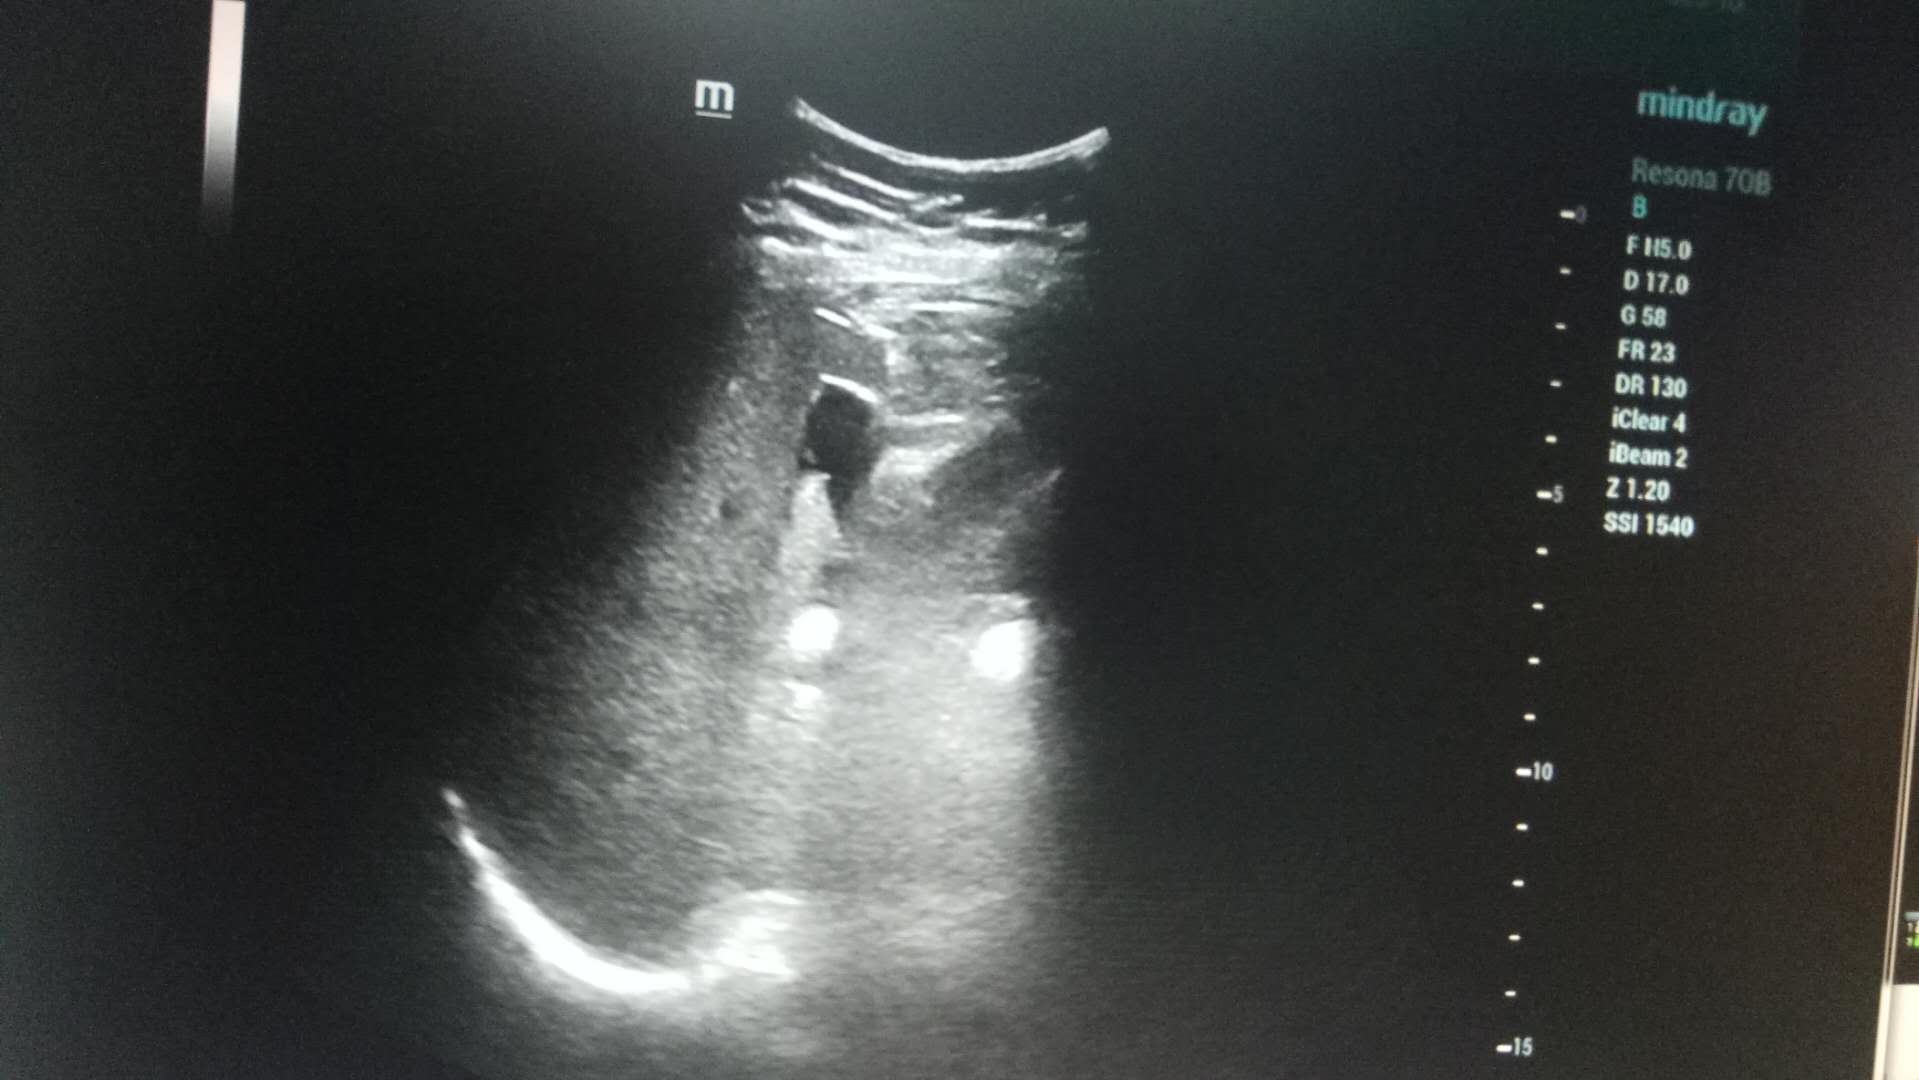

近日,男同视频 超声科在高陵区医院成功开展了一例超声引导下肝囊肿抽吸硬化治疗术。患者前段时间查出肝囊肿,因开腹手术风险性大且痛苦,遂联系了高陵区医院超声科,在男同视频 超声科主任展小军与对口支援医生杨艳秋的紧密配合下,短短30分钟,通过一根穿刺针,直径近7cm的肝囊肿就被完全抽吸硬化完毕,患者生命体征平稳,休息几小时后已活动自如。

超声介入微创诊疗技术是在实时超声的监视和引导下,完成各种穿刺、活检以及抽吸、插管、注药治疗等操作,达到与外科手术相当的效果,具有创伤小、恢复快、无辐射、介入治疗定位精确等优点。可治疗全身各部位囊肿,尤其是巧克力囊肿效果更佳,还有全身各部位肿瘤的活检和治疗,超声引导下微创治疗是未来医学发展方向。